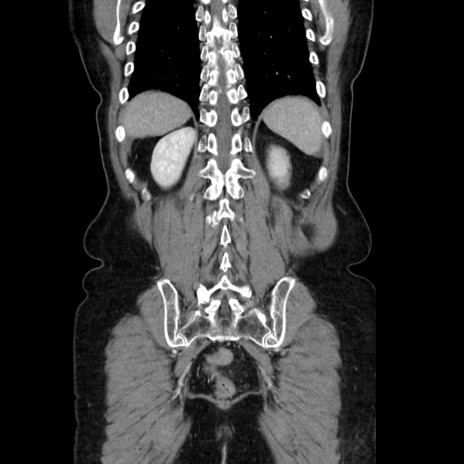

症例5(冠状断像)

【症例】70歳代女性

【主訴】お腹が張る

【現病歴】1週間くらい前から腹部膨満の自覚あり。昨日夜から増悪したため、本日救急外来受診。

【身体所見】意識清明、BT 36.5℃、BP 165/106mmHg、HR 80bpm、SpO2 98%、腹部:膨満、軟、自発痛・圧痛なし、触診にて不快感あり、腸蠕動音:減弱

【データ】WBC 12600、CRP 1.04